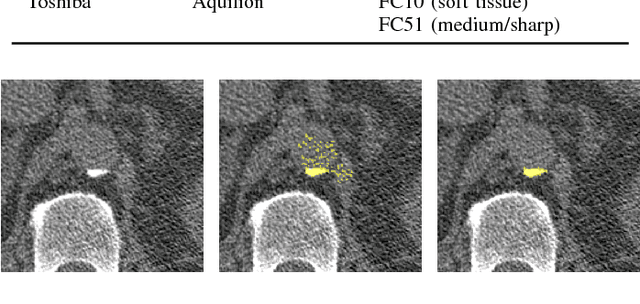

Abstract:Early detection of lung cancer has been proven to decrease mortality significantly. A recent development in computed tomography (CT), spectral CT, can potentially improve diagnostic accuracy, as it yields more information per scan than regular CT. However, the shear workload involved with analyzing a large number of scans drives the need for automated diagnosis methods. Therefore, we propose a detection and classification system for lung nodules in CT scans. Furthermore, we want to observe whether spectral images can increase classifier performance. For the detection of nodules we trained a VGG-like 3D convolutional neural net (CNN). To obtain a primary tumor classifier for our dataset we pre-trained a 3D CNN with similar architecture on nodule malignancies of a large publicly available dataset, the LIDC-IDRI dataset. Subsequently we used this pre-trained network as feature extractor for the nodules in our dataset. The resulting feature vectors were classified into two (benign/malignant) and three (benign/primary lung cancer/metastases) classes using support vector machine (SVM). This classification was performed both on nodule- and scan-level. We obtained state-of-the art performance for detection and malignancy regression on the LIDC-IDRI database. Classification performance on our own dataset was higher for scan- than for nodule-level predictions. For the three-class scan-level classification we obtained an accuracy of 78\%. Spectral features did increase classifier performance, but not significantly. Our work suggests that a pre-trained feature extractor can be used as primary tumor origin classifier for lung nodules, eliminating the need for elaborate fine-tuning of a new network and large datasets. Code is available at \url{https://github.com/tueimage/lung-nodule-msc-2018}.